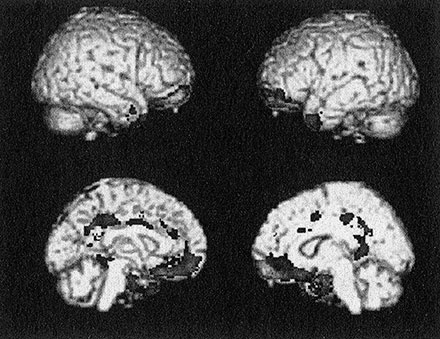

Рис. 8. Результаты первого анализа данных структурной МРТ по осужденным психопатам, собранные с помощью мобильного томографа. Затененные области – это те участки мозга, которые атрофированы у взрослых психопатов-преступников мужского пола. Они соответствуют большей части паралимбической системы (см. при-меч. 3)

Я схватил стул и чуть отодвинул Прашантха от компьютера. У психопатов оказалась пониженная плотность серого вещества в глазнично-лобной коре, миндалевидном теле, гиппокампе, островке, височном полюсе и передней и задней поясной коре. Вся паралимбическая система была аномальна. Я даже не представлял себе такого эффектного результата. Он меня сразил.

Это был один из тех редких моментов в жизни ученого, когда полностью подтверждается гипотеза – гипотеза, которую мы со всей моей лабораторией оттачивали и совершенствовали годами. Я велел Эльзе запомнить этот день на всю жизнь. У психопатов действительно оказался аномальный мозг; мы получили надежное доказательство.

Я в том же месяце представил данные о плотности мозга психопатов на заседании исследовательской сети при Фонде Макартуров. Профессора права и судьи долго смотрели на изображение, обдумывая, какие все это может иметь следствия. Я напомнил, что мы установили корреляцию, но не причинно-следственную связь.